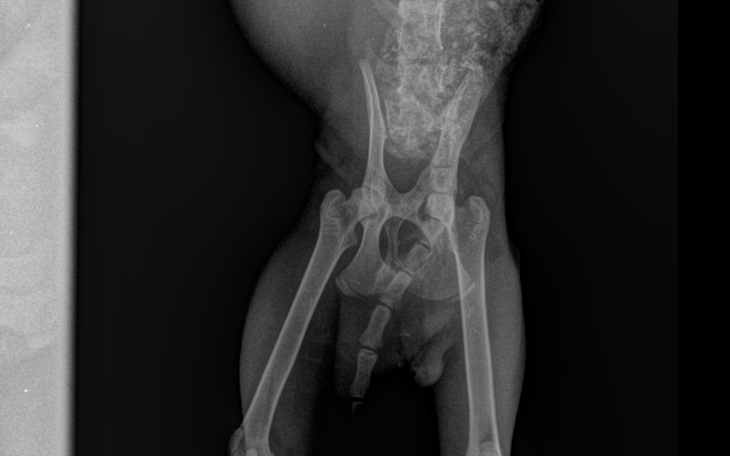

RTG wykonane w Żninie wykazało stare i krzywo zrośnięte złamanie miednicy. Do tego przerwanie rdzenia kręgowego tuż przy ogonie. Ogon został wyrwany.

Niestety spora krzywizna miednicy okazała się przyczyną tego, że kot nie mógł się wypróżnić, było zbyt wąsko.